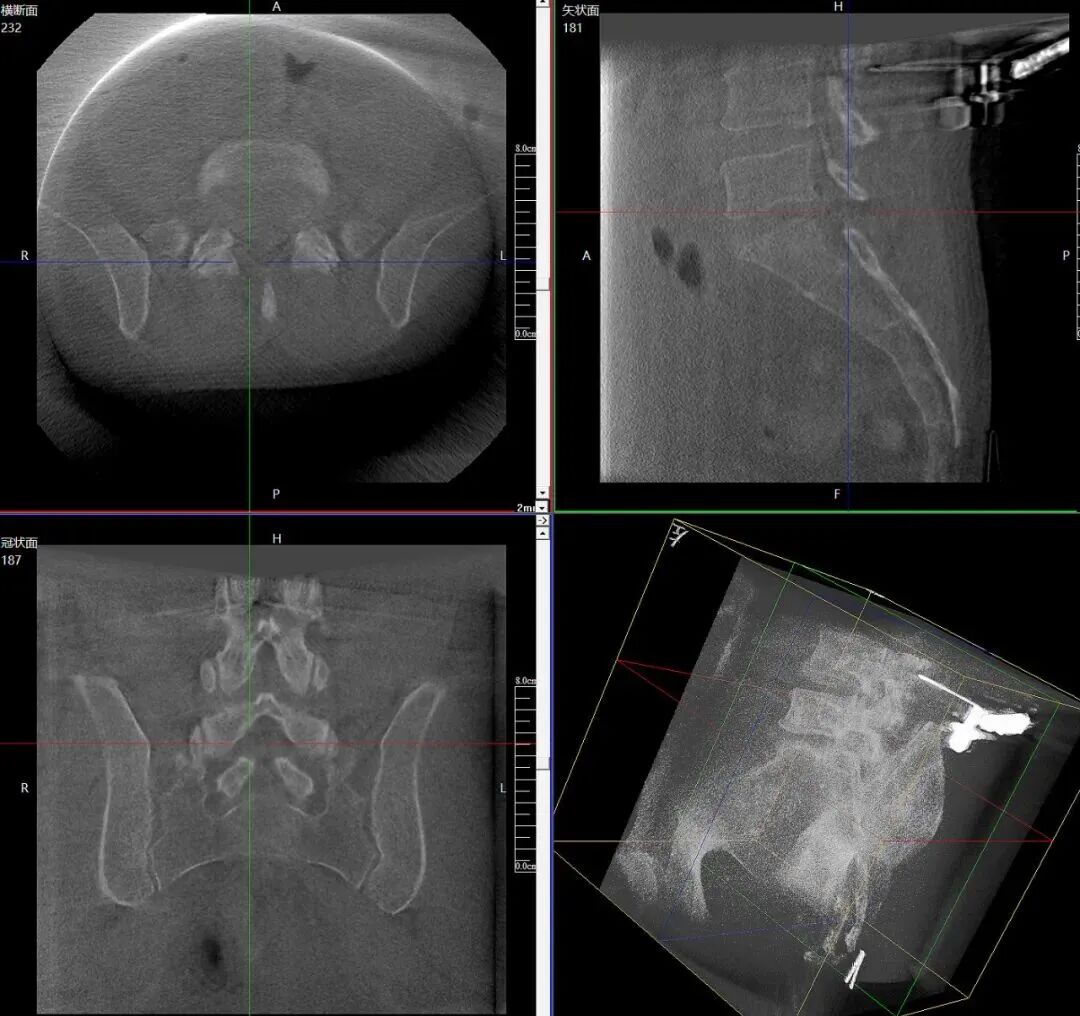

手术过程中,平板三维C形臂重建的高清三维影像,将患者腰椎的解剖结构、病灶位置等细节清晰呈现。机器人机械臂根据医生预设手术路径自动定位导向,医生依托椎间孔镜技术,仅在患者体表做1-2厘米的微小切口建立工作通道,精准摘除突出髓核、松解神经根,全程微创,确保了整个手术过程安全、高效。

术中三维成像